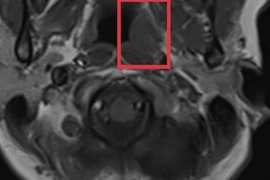

Một bệnh nhân trẻ tuổi có khối u tuyến giáp kích thước lớn, ác tính xâm lấn, di căn hạch cổ vừa được các bác sĩ Bệnh viện Bãi Cháy phẫu thuật thành công.